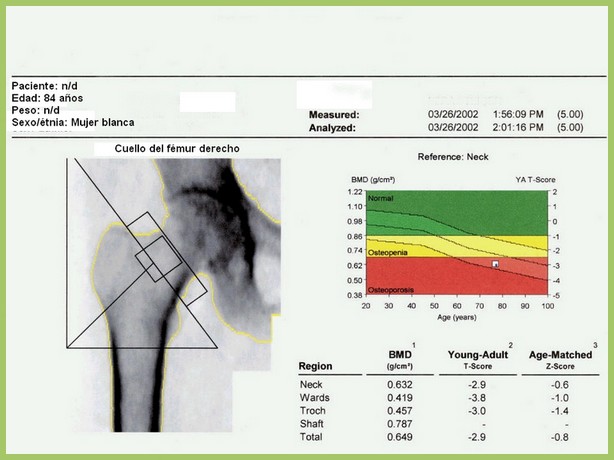

En este estudio argentino, la mitad de las densitometrías se pidieron en mujeres que no cumplían los criterios recomendados de edad o de riesgo aumentado para justificar el rastreo de osteoporosis. Salud Colectiva, octubre de 2016

Osteoporosis: umbrales de intervención adaptados a cada país

Una revisión sistemática de los umbrales de intervención basados en la herramienta FRAX para la estimación del riesgo de fractura. Archives of Osteoporosis, 27 de julio de 2016